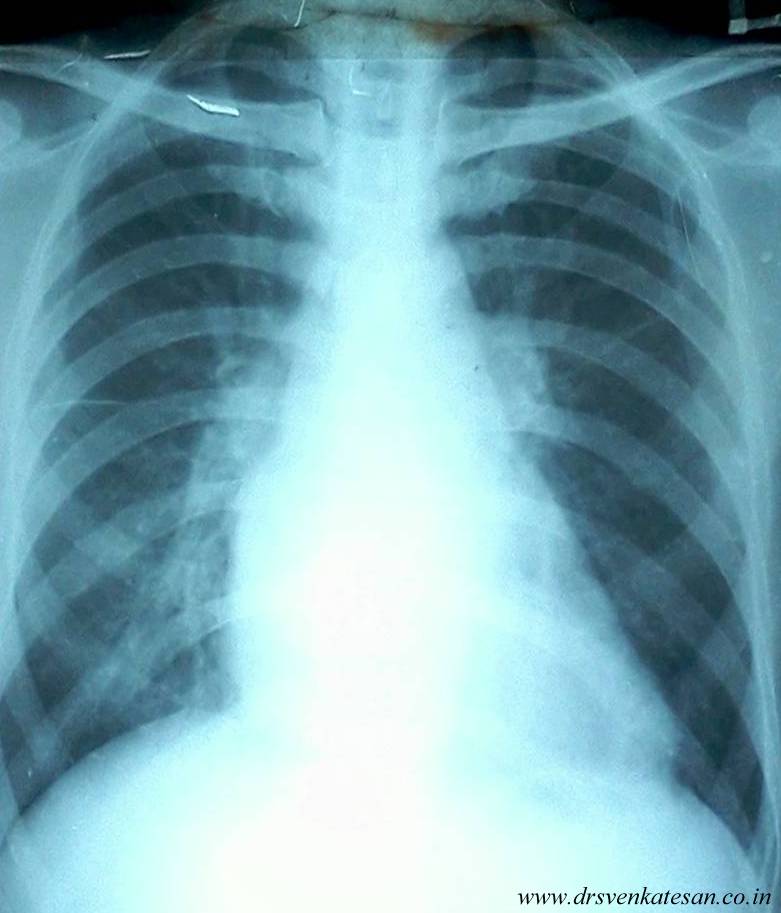

Here is an X-ray of classical rheumatic mitral stenois with a mitral orifice of .8 square cm.

Why the left heart border is straight in mitral stenosis ?

It is due to 4 factors.

- Hypoplastic aorta

- LAA

- PA

- Under filled LV

Note :

- This straightening occurs only in isolated , severe forms of mitral stenosis as it requires under filling of left ventricle and Aorta.

- Significant mitral regurgitation will lift the lower end of straight line .

- In associated aortic valve lesions especially in aortic regurgitation the straightening can not occur as LV and Aorta continues to be conspicuous.

- If mitral stenosis causes severe PAH and tricuspid regurgitation , RV can become huge and form the left heart border and distort the straight line.